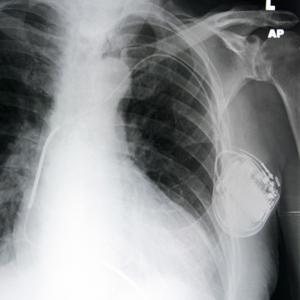

FAITH LAPIDUS: A pacemaker is a small device that doctors place in people with an abnormal heartbeat. If a heart beats too slowly, the device will use electrical signals to help set a normal rate. Some pacemakers include a defibrillator, which gives a shock if the heart beats too fast.

X-ray showing a pacemaker

A big problem, however, is cost. Buying and implanting a pacemaker costs from 5,000 to 15,000 dollars. Yet doctors at the University of Michigan think they know a way to lower that cost. The idea is to reuse pacemakers.